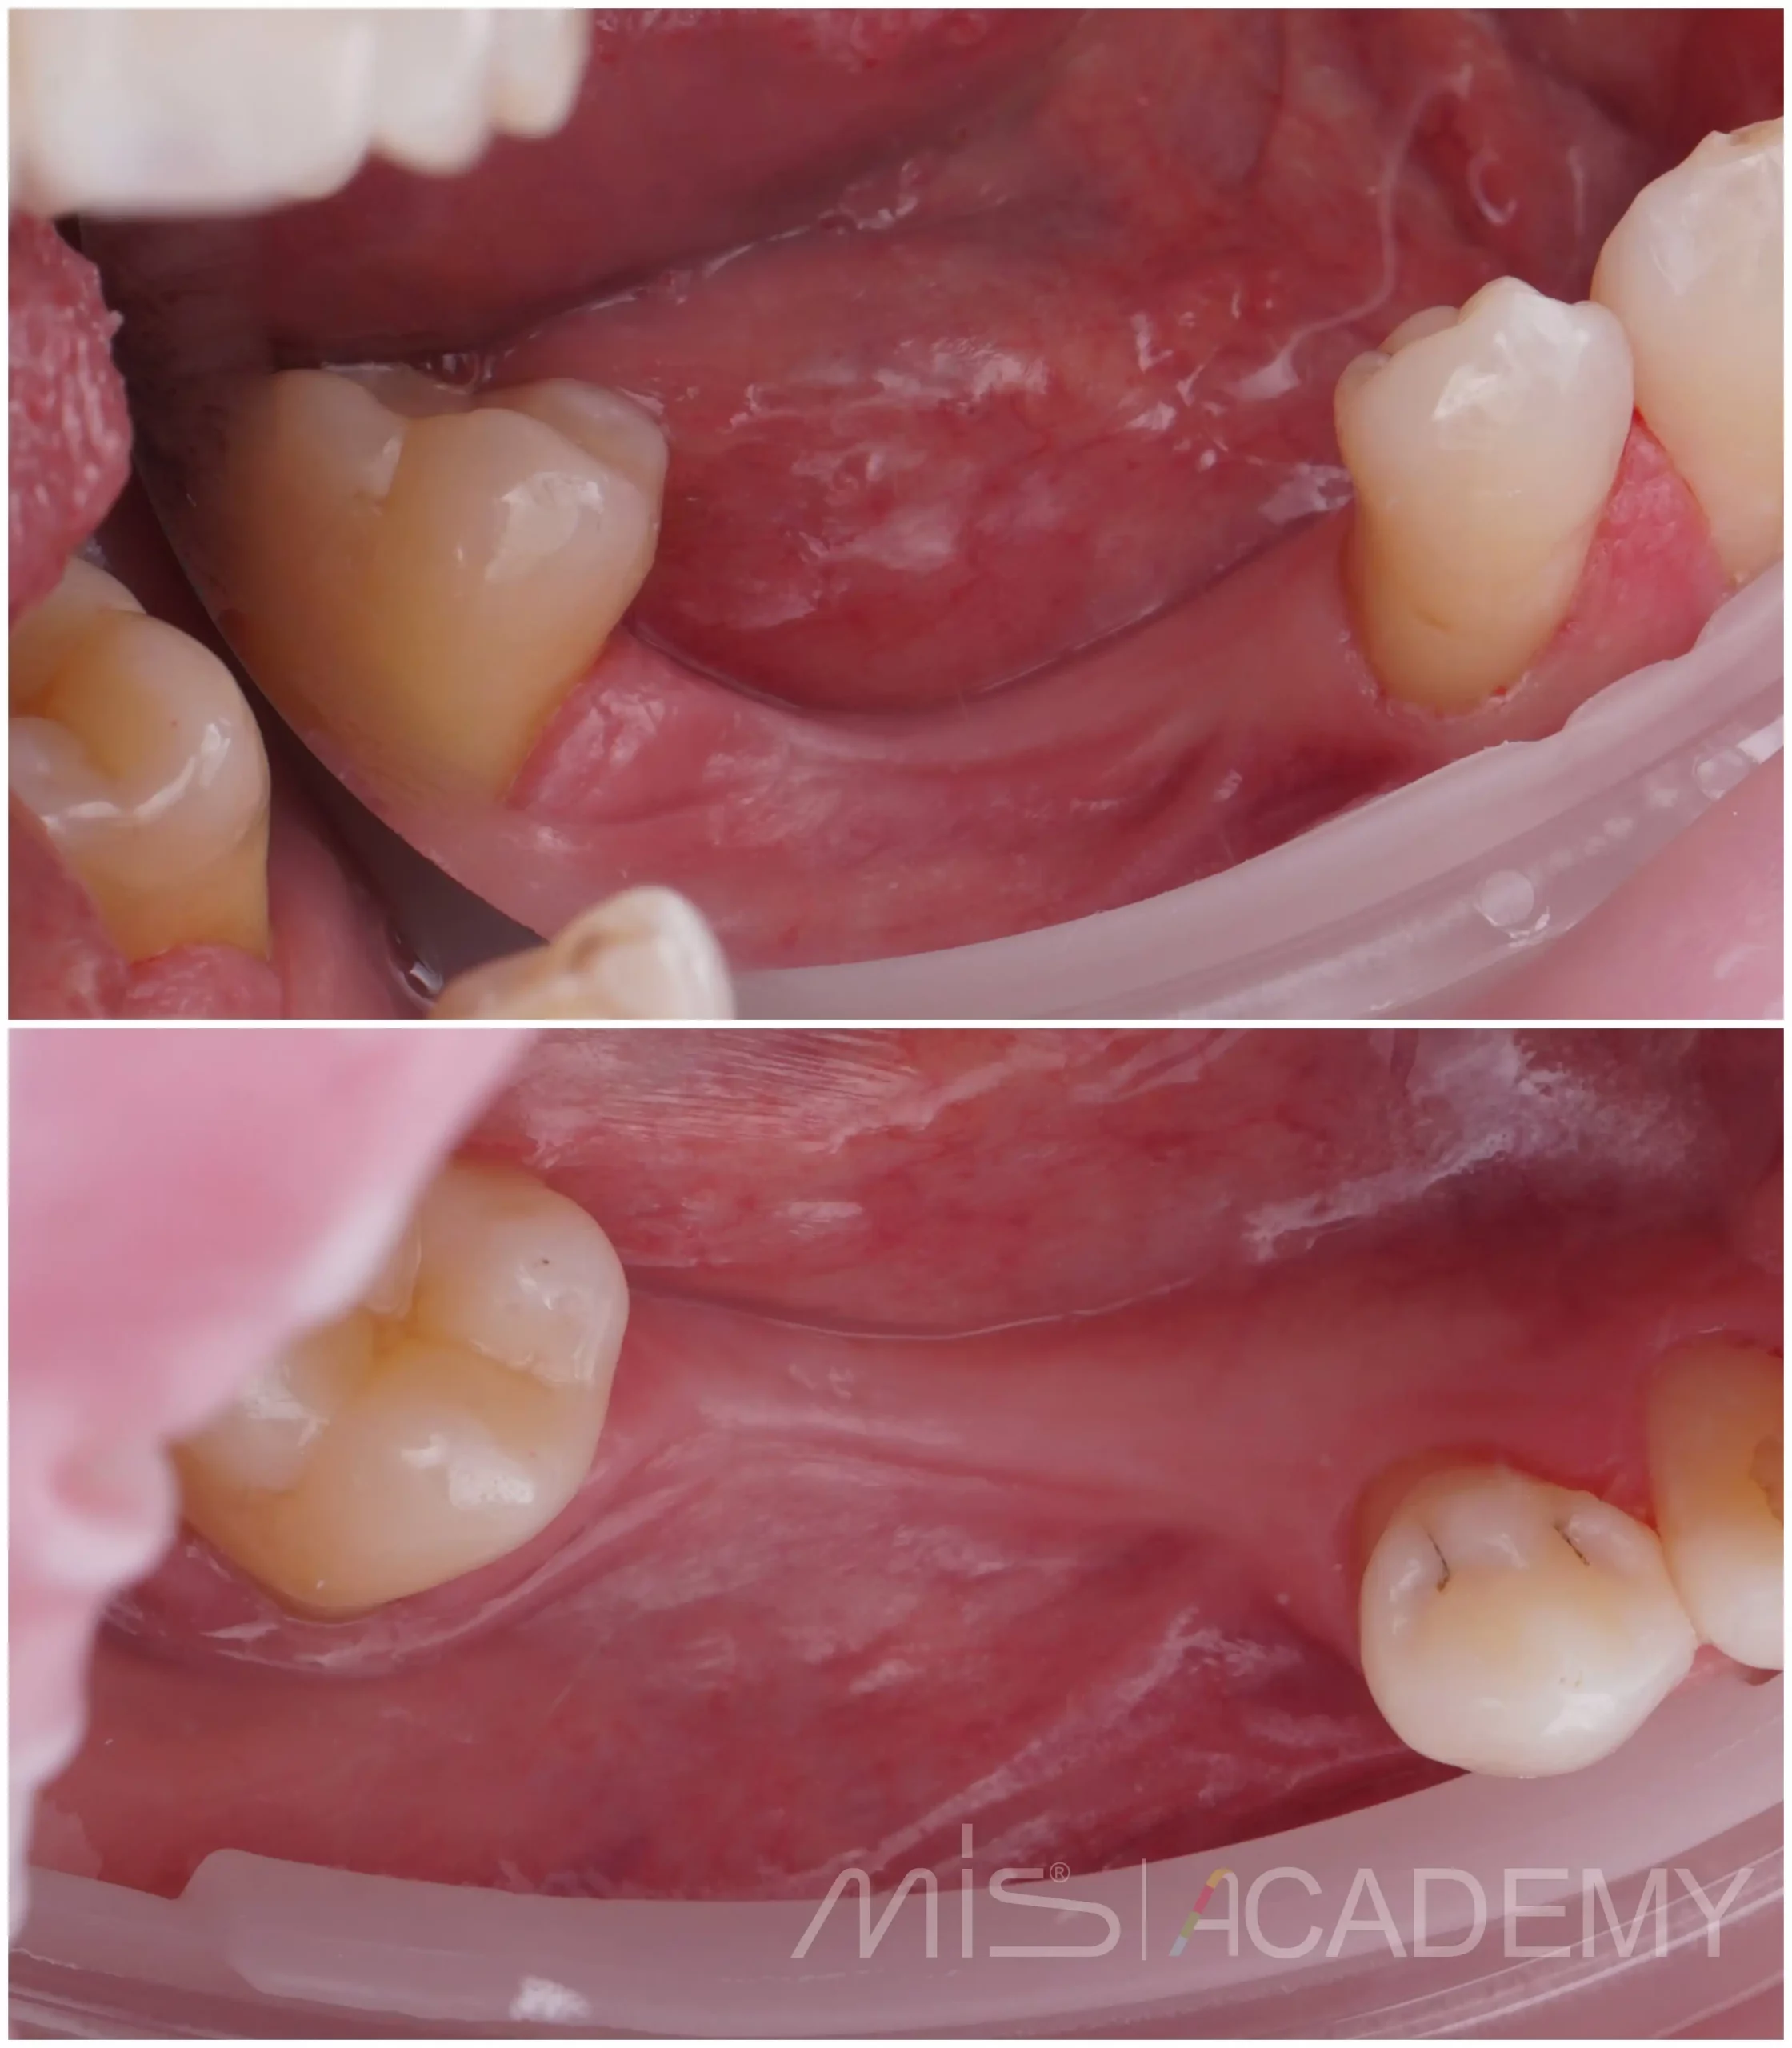

Пациент изначально обратился за костной пластикой, но после полноценного анализа данных и детального планирования мы предложили альтернативное, более рациональное решение.

— Мягкие ткани дополнительно доработали: выполнена пластика ССТ на фдм методом пончо и вестибулярно.